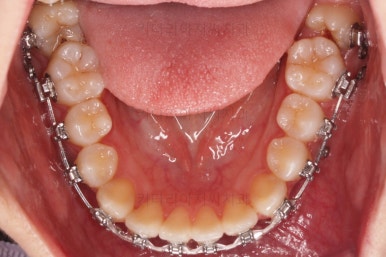

점점 뒤쪽 치아가 바로 일으켜 세워지고 있네요.

생각보다 많이 썩은 상태였어요.

앞쪽 치아 하방으로 갇혀 있으신 훨씬 심각한 상태까지 충치가 진행되었던거죠.

우측 상단에 보이던 어금니도 바로 세운 뒤, 치료를 했습니다.(골드 인레이)

왼쪽 상단으로 보이던 치아도 치료를 했어요.

좌우의 치아가 재료가 차이가 나는데 한 쪽은 튼튼하고 오래 쓸 수 있고, 광범위한 부위에 맞는 인레이라는 치료방법이고요.

왼쪽 치아도 인레이가 추천되는 상황이었지만 경제적인 사정을 고려해서 일단은 건강보험이 적용되는 재료인 GI(지아이)라는 재료로 치료를 했어요.

성질이 약한 단점이 있어서 주기적인 체크가 굉장히 중요합니다.

기타 부위들의 디테일을 좀 더 맞춰주고 치료를 종료합니다.